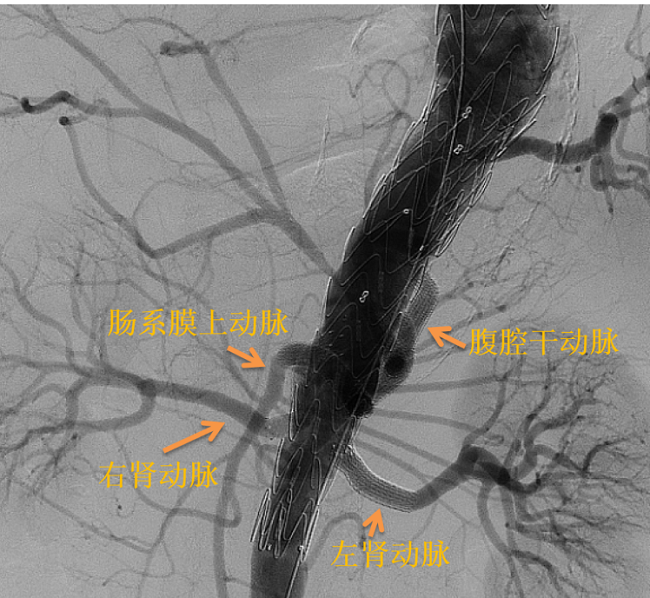

▲ 术中造影:胸腹主动脉瘤

▲ 支架释放后造影:内脏四分支通畅

在手术麻醉科主任胡强夫、医生郭佩垒的配合下,王兵教授带领血管外科崔文军主任、安乾副主任、任菲副主任医师、王梦宇医师向这一高难度手术发起挑战。凭借丰富临床经验及精准介入手术技能,在杨先生的左上肢、腹股沟部行穿刺,通过造影实时确认胸腹主动脉瘤位置。在DSA监视屏监测及导丝的引导下,王兵教授团队成功将体外开窗的覆膜大支架精确植入到动脉瘤部位,并将覆膜小支架超选置入内脏4分支腹腔干动脉、肠系膜上动脉、双侧肾动脉内,从而将血流与薄弱的瘤壁隔绝,不仅消除了瘤体破裂、出血隐患,还保留了内脏分支血流的通畅,防止胃肠道、肝胆胰脾、双肾等重要脏器的缺血现象。经过长达5个小时尽心尽力、一丝不苟的操作,王兵教授团队成功拆除了这颗不定时“炸弹”,杨先生转危为安。术后两周CTA复查提示“胸腹主动脉瘤隔绝效果佳,内脏动脉支架通畅”,恢复效果良好。